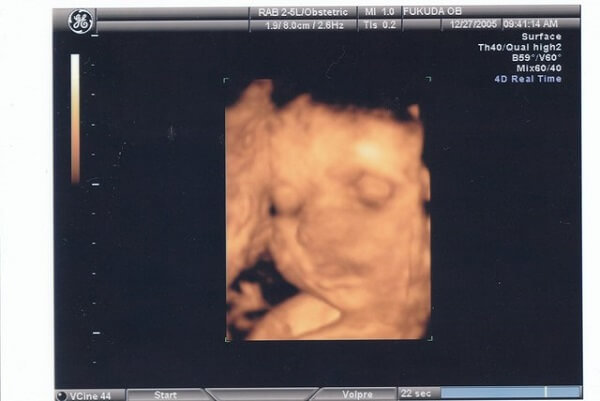

妊娠8ヶ月(28~31週)かぼちゃ1個くらいの重さ

身長約43㎝、体重約1800g。主要な器官はほぼ完成します。万が一早産になってしまっても、大部分の赤ちゃんは問題なく成長できるくらいにまでなっています。

ですが、産まれてすぐに呼吸を始めるのに大切な器官である肺だけはまだ未熟です。これから、産まれるときまでゆっくりと成熟していきます。

エコーでもしっかりとお顔らしいものも見え、角度によっては表情もみえます。手や足をばたつかせる様子は、お腹からでてきた赤ちゃんと変わりなくとても愛らしいです。